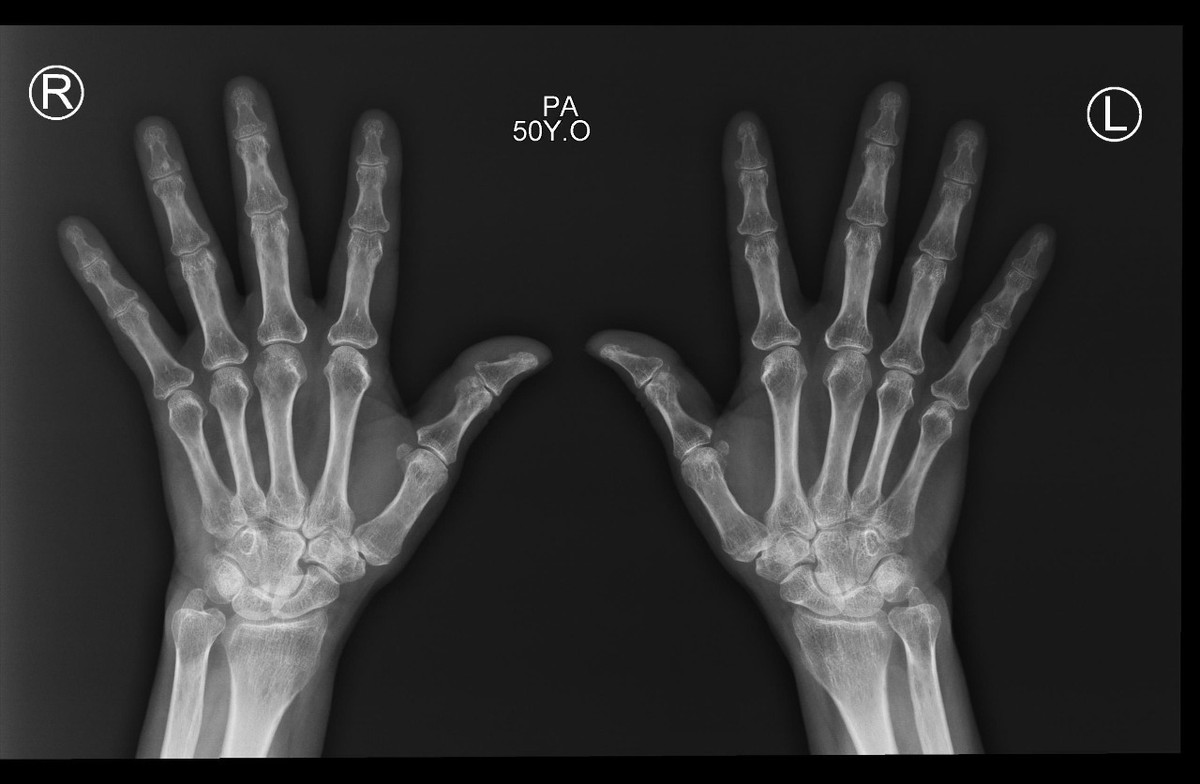

في كل يوم اسمع أمي ومن هم حولي من كبار السن يعانون من الآم مستمرة في العظام تحديدًا في منتصف الظهر والورك الأيمن والأيسر والركبتين، فهذه المناطق أرى أن أكثر كبار السن يشتكون منها. المراجعات الخاصة بالمسشتفى بلا فائدة، الأدوية كذلك. تأثرت صحة أمي كثيرًا فلم تعد تمارس اعمالها كما في السابق ولم تعد حتى تقدر على طلوع الدرج ولا الجلوس كثيرًا. وهذه بعض صور الخاصة بأشعة العظام عندما تم فحصها

- يوجد لدي نتائج تحليل البول وكذلك تحليل الدم في حال اردت مساعدتي بخصوص خشونة الركب